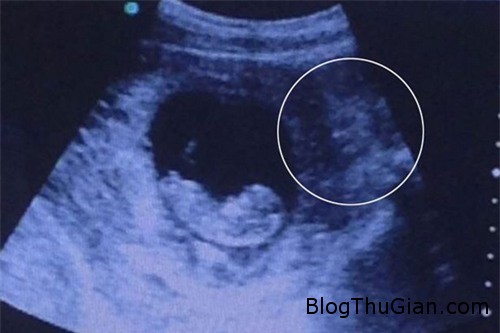

Nếu nhìn qua, bạn sẽ thấy hình ảnh này bình thường như bao hình ảnh siêu âm thai khác với thai nhi đang nằm trong bụng mẹ. Vậy tại sao bức ảnh lại thu hút tới 500.000 lượt xem chỉ sau 1 ngày được đăng tải trên mạng?

Một phát hiện được chia sẻ và ngay lập tức đã thu hút những người hiếu kỳ, khiến người xem không khỏi lạnh gáy đó là bên phải của bức ảnh có một nhân vật nhìn rất lạ. Hình ảnh này cũng đã được đăng tải trên imgur với tiêu đề: “Hình ảnh siêu âm thai của một người bạn. Bạn đã nhìn thấy gì?…”

Bức ảnh khiến người xem lạnh gáy với hình ảnh lạ bên phải.

Nhìn kỹ bức ảnh này, rất nhiều ý kiến đã được đưa ra: “Hình ảnh bên phải rất giống nữ thần Hindu.” Ý kiến khác lại cho rằng: “Giống một nàng tiên cá” hay “Một con quỷ dữ”…